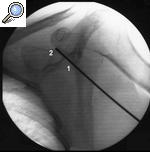

La aguja se introduce perpendicularmente hasta que se localiza el nervio o se llega a tocar el hueso en la fosa supraescapular (fig. 3). Si sucede esto, se debe dirigir la punta de la aguja ligeramente hacia medial hasta que se localice el nervio.

Figura 3. Bloqueo del nervio supraescapular con control radiológico. Nótese la varilla (1) marcando la fosa supraescapular (2).